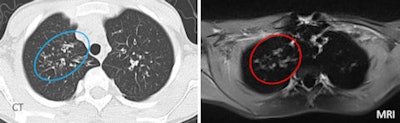

![]() |

| Sometimes MRI was misleading, as in the case of a 22-year-old male patient with mild cystic fibrosis disease. Vessel depiction in MRI mimicked a large bronchiectasis of the right upper lobe. Moreover, MRI propeller sequence produced linear artifacts that derive from k-space reconstructions. The artifacts appear as lines in the lung parenchyma, creating false bronchi. All images courtesy of Dr. Perluigi Ciet. |